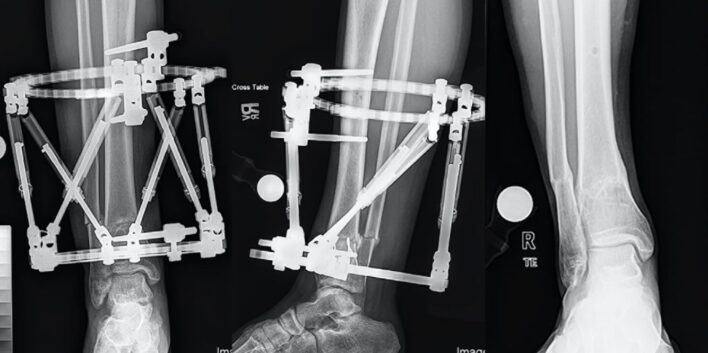

CT và MRI

MRI và CT với khả năng dựng hình 3D là các phương pháp tương đối chính xác để chẩn đoán biến dạng xoay ở chi dưới. Các đo lường được lấy từ các nhát cắt 2D qua cổ xương đùi, đầu dưới xương đùi, đầu trên xương chày, và gọng khớp cổ chân để xác định mức độ xoay. Có nhiều kỹ thuật đo lường đề nghị cho mỗi phân đoạn tùy theo các tác giả. Việc sử dụng CT nhiều lần có thể bị hạn chế ở trẻ nhỏ do tia xạ, ngược lại MRI lại đắt tiền và tốn thời gian hơn mặc dù không gây nhiễm xạ cho trẻ.

Các kỹ thuật chỉnh xương thay đổi, bao gồm đinh nội tuỷ, mổ chỉnh xương, cố định ngoài, nẹp vít … có hoặc không có điều chỉnh mô mềm kèm theo. Có thể kèm theo điều chỉnh chênh lệch chiều dài chi nếu có.